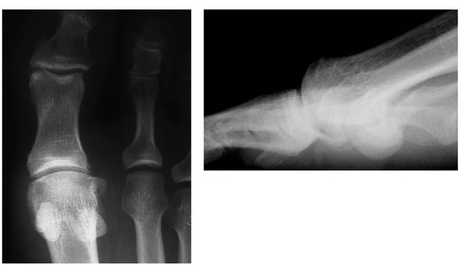

Контрактура суставов и тыльный подвывих большого пальца у профессионального футболиста. А, Внешний вид первого пальца. В, Рентгенограмма в боковой проекции.